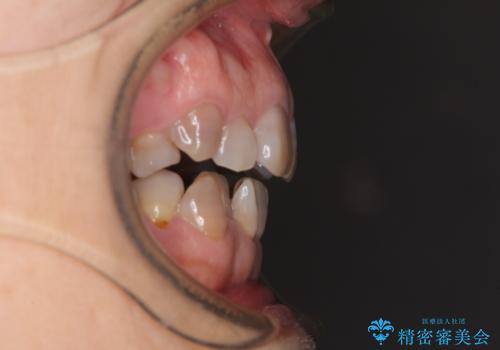

- 小さいころからの歯の変色と矯正治療の後戻りを気にして来院された患者様です。

気になる変色歯を仮歯に変え、その後歯列不正を矯正治療で改善し、最後にオールセラミッククラウンにて補綴治療することとしました。